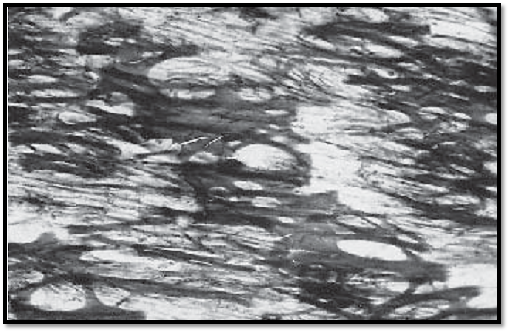

Descending Thoracic Aorta

This cross-section of the tunica media from the descending aorta shows strong, in some places undulating elastic membranes (stained blue-violet). In a vertical section, they appear as fibers with intertwined muscle cells. At their insertion sites, the muscle fibers create the image of brush strokes. The myocytes encircle the aorta, forming right- and left-handed spirals. This creates a fishbone pattern in a cross-section. In this arrangement, the smooth muscle cells can regulate the tensile force of the elastic fiber network . The collagen connective tissue is stained green. A vessel of the vessel wall 1 ( vas vasis ) is visible in the left corner of the image.

1 Vessel with erythrocytes

2 Smooth muscle cells, myocytes

Stain: Masson-Goldner trichrome; magnification: × 400